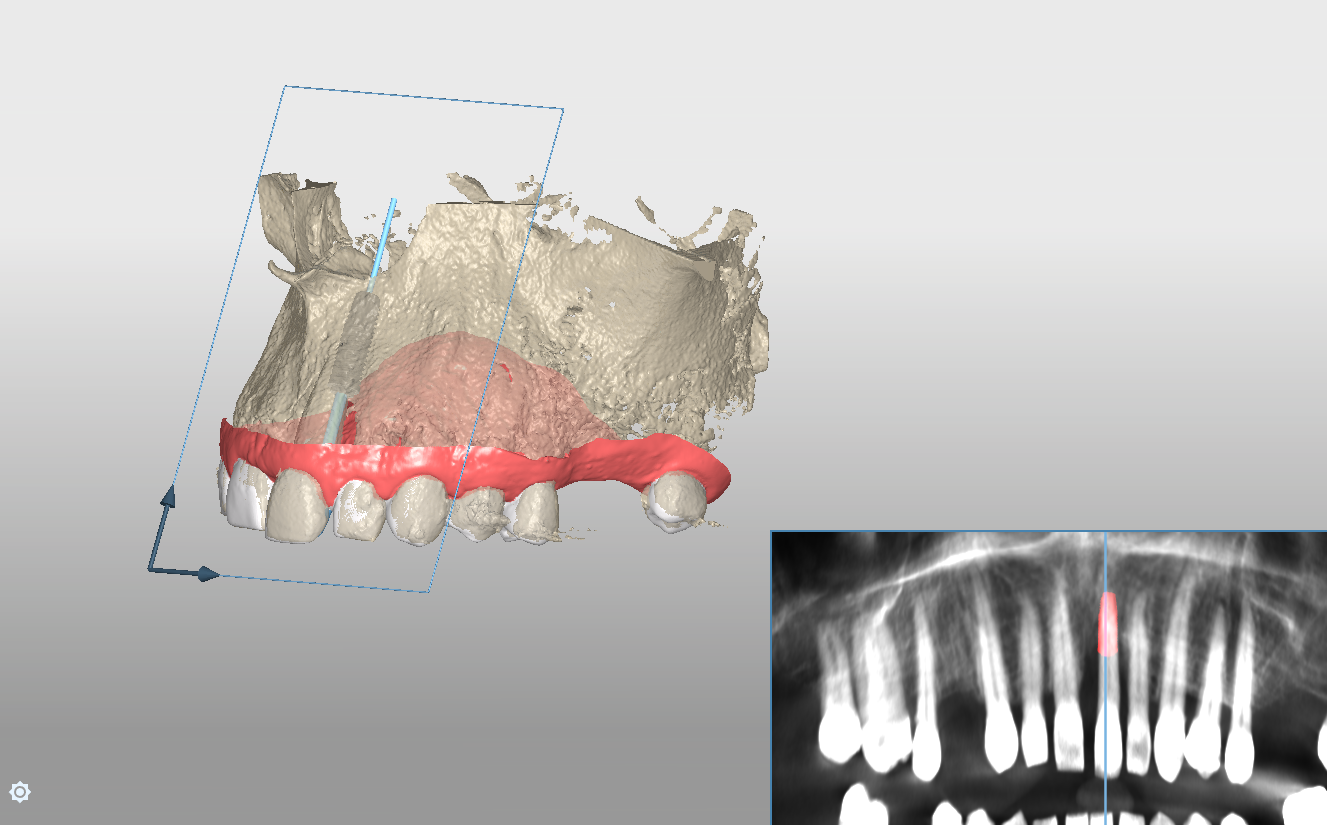

Pre-operative planning was performed using the DICOMLAB digital planning platform. The workflow included a pre-operative CBCT scan of the upper jaw and a digitalintraoral scan.

These datasets were merged within the DICOMLAB software to allow prosthetically driven implant planning.

Planned implant:

DSI Conical Implant - 4.3 mm diameter, 13 mm length.

A custom surgical guide was fabricated using the DICOMLAB open platform, which allows surgical guide production for most implant systems.

The DICOMLAB surgical guide was positioned, and the implant was placed according to the digital plan.